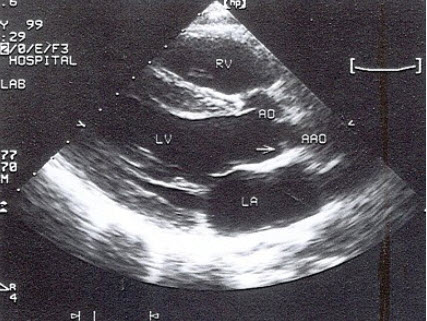

42、填空题

如图,根据二尖瓣M型超声心动图特征,可见CD段呈_______样改变。